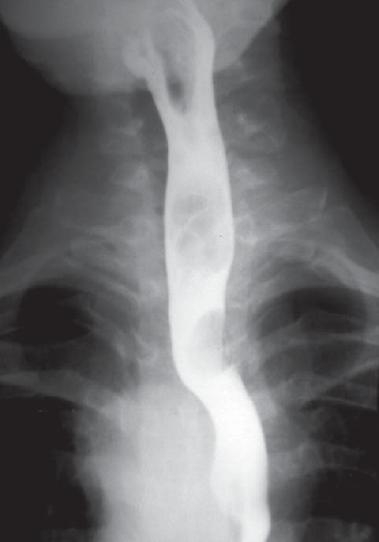

An initial upper endoscopy, an esophagogram, and an x-ray of the thorax were performed. The endoscopy showed no alterations, while the esophagogram showed lateralization of the esophagus toward the left through the aortic arch and the descending aorta, but no other findings (figure 1). The thorax x-ray showed mediastinal widening and curvature of the tracheal air column on the superior mediastinum with a posterior correction in its distal route (figure 2). Based on these results the decision was made to proceed with an enhanced contrast thorax CT scan. This scan showed an anatomical variation: a right aortic arch was present with an aberrant left subclavial artery running around the trachea and esophagus with variants in the carotid arteries (figure 3). To achieve a better description of these alterations magnetic angioresonance of the thorax was performed. It confirmed the tomographic findings and showed a dilatation at the end of the aortic arch (Kommerell's diverticulum) which is the point of origin of the aberrant left subclavial artery. It also showed a common point of origin for the common carotid arteries (bicarotid trunk) (figure 4). The patient was evaluated again following these results (nine months after onset of symptoms). Symptoms persisted with the same frequency and intensity as at her first visit to our services. No new symptoms had developed. Consequent to these findings she was referred to vascular surgery for a determination regarding the need for surgery. This evaluation is pending as of this writing.Figure 1. Esophagram showing displacement of esophagus to the left secondary to the location of the aortic arch and descending aorta.

An adequate clinical history when dysphagia appears can cause suspicion of organicity, however, as mentioned; the majority of patients are asymptomatic. Their physical exams tend to be normal, especially if other vascular alterations are not present. In some cases patients' have differences between left and right arm blood pressure measurements from those normally found. This could indicate the presence of one or more vascular alterations; however this finding is not very specific (1, 7, 14). A simple x-ray of the thorax may show mediastinal widening due to the existence of Kommerell's Diverticulum or even the presence of right aortic arch (figure 1), although other imaging techniques including digital technology may be needed (4, 16, 23, 24). Endoscopic study of the esophagus is commonly used for the majority of these patients. It is indicated with findings of peptogastric and esophageal pathologies when extrinsic compression in the posterior wall of the esophagus has been observed. In some of these cases this is even more evidently indicated when the arm on the side of the compromised vessel is raised or when impacted food is found in the affected area (6, 14, 17, 23). Endosonography may confirm the vascular origin of the compression when it is evident in the endoscopy (5, 23). Esophageal manometry usually shows unspecified alterations without being pathognomonic for a diagnosis nor adequate for referral to surgery. Among the symptoms found is high pressure zones synchronized with arterial pulsation and with the wave of the EKG. Others include absence of relaxation after swallowing is stimulated and evidence of high peristaltic pressure near the compression site. In conjunction with mechanical effects related to the vessel, these motor alterations may contribute to the development of dysphagia. Effects related to the vessel are more evident when the arm is raised causing increased vascular flow through the aberrant artery (14, 17, 25, 26). An esophagogram must always include lateral and oblique film to improve diagnostic performance and avoid a filing defect which could be inadvertently overlooked. An oblique ascending image to the left or to the right according to the side of the aberrant vessel to the level of the third or fourth thoracic vertebrae is the most common finding. However, esophagograms are normal in up to 40% of patients, and there are no clear relations between esophagogram findings and manometry results for all patients. In some cases performing the exam when a pill has been taken makes it easier to locate the defect and allows reproduction of the patient's symptoms (6, 14, 17, 24, 26). Although angiography has been the gold standard for diagnosis of vascular abnormalities, advances in diagnostic imaging technology have transformed made angiographic studies using CAT scans and MRIs into the best performing methods. This is due to their availability, non-invasive characters and their capacity to discriminate among other vascular alterations which may be present in patients (Figures 3 y 4). With the development of multi-detector tomography and 3-D reconstructions it is much easier to determine anatomical characteristics of the aortic arch (3, 6, 16, 11, 12, 17, 24).Treatment